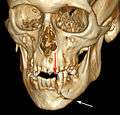

Rigid internal fixation of parasymphasis fracture of the mandible. White arrow marks fracture, black arrow marks arch bar on lower teeth

Rigid internal fixation of right condyle fracture with mini-plate on the neck of the condyle. Black arrow marks right earlobe, white arrow marks head of the condyle